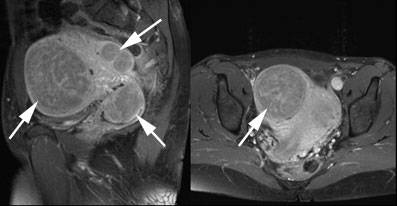

Gebärmutterknoten

Magnetresonanztomographie bei einer Patientin mit Gebärmutterknoten. Die Gebärmutter ist stark vergrössert und die gutartigen Knoten (Pfeile) nehmen nahezu das gesamte kleine Becken ein.